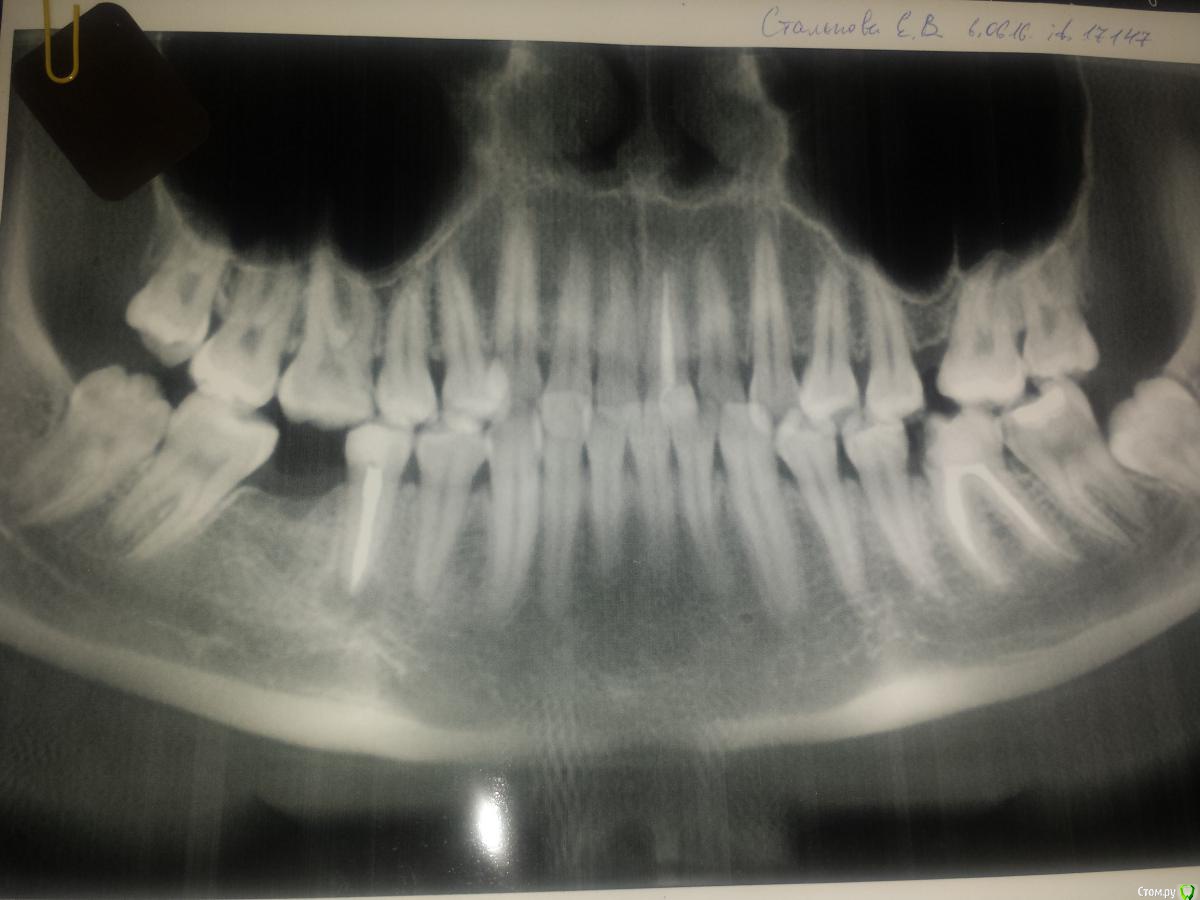

EkaterinaVVL Опубликовано 23 июня, 2016 Поделиться Опубликовано 23 июня, 2016 Здравствуйте, помогите пожалуйста возможно ли сохранить зуб? После проведения ОПТГ обнаружили кисту зуба (5-ка снизу) была в нескольких клиниках, мнения врачей расходятся одни говорят удалять, другие лечить. Посмотрите пожалуйста и подскажите что делать в такой ситуации? Целесообразно удаление? У меня 6-ки нету вот и переживаю как дальше, если все таки удалять... но и с очагом инфекции ходить опасно тк планируется беременность. Один врач заметил кисту на 6-ке снизу слева, есть ли там киста?(понимаю что скорее всего нужно делать прицельный снимок зуба). После лечения(удаления) планирую ставить брекет-систему. Фото ОПТГ+ прицельный снимок(5-ки, фото правда не очень) прилагается.Очень нужна помощь, заранее большое спасибо Ссылка на комментарий

___49___ Опубликовано 24 июня, 2016 Поделиться Опубликовано 24 июня, 2016 (изменено) Вариантов для сохранения 2 .- перелечить канал у грамотного эндодонтиста ..- произвести резекцию корня у грамотного хирурга стоматолога ( так как рядом выход нервно-сосудистого пучка ).Первый вариант предпочтительнее , но при возникновении затруднений( непроходимый канал и т.п.) возможен и вариант 2 . Оба варианта потребуют рентген контроля, в вашем случае если после пройденного лечения в скором времени вы забеременеете , врачу придется ориентироваться только на клинические проявления (при отрицательной динамике будет показано удаление зуба), при положительной динамике после родов , вам проведут рентген контроль после которого можно будет сказать происходит восстановление костной ткани или нет - шанс не 100% но все равно достаточно хороший на сохранение зуба ( исходя из предоставленной вами информации т.к. возможны нюансы ....форум - это не очный прием ). Изменено 24 июня, 2016 пользователем ___49___ Ссылка на комментарий

Bier Опубликовано 25 июня, 2016 Поделиться Опубликовано 25 июня, 2016 Канал вроде хорошо пролечен. Надо залезть в зуб еще раз, если там не пропустили доп. канал, то можно подумать о резекции (только грамотные нужны специалисты, чтобы по "старинке" не сделали) с ретроградной пломбировкой. 2 Ссылка на комментарий

vse32 Опубликовано 28 июня, 2016 Поделиться Опубликовано 28 июня, 2016 Надо залезть в зуб еще раз, если там не пропустили доп. канал, то можно подумать о резекции Периодически вижу снимки на которых красивая пломбировка и киста. Практически всегда там гутта. Подозреваю недостаточную медобработку. Качественный ретрит - вероятнее всего решит проблему. Ссылка на комментарий